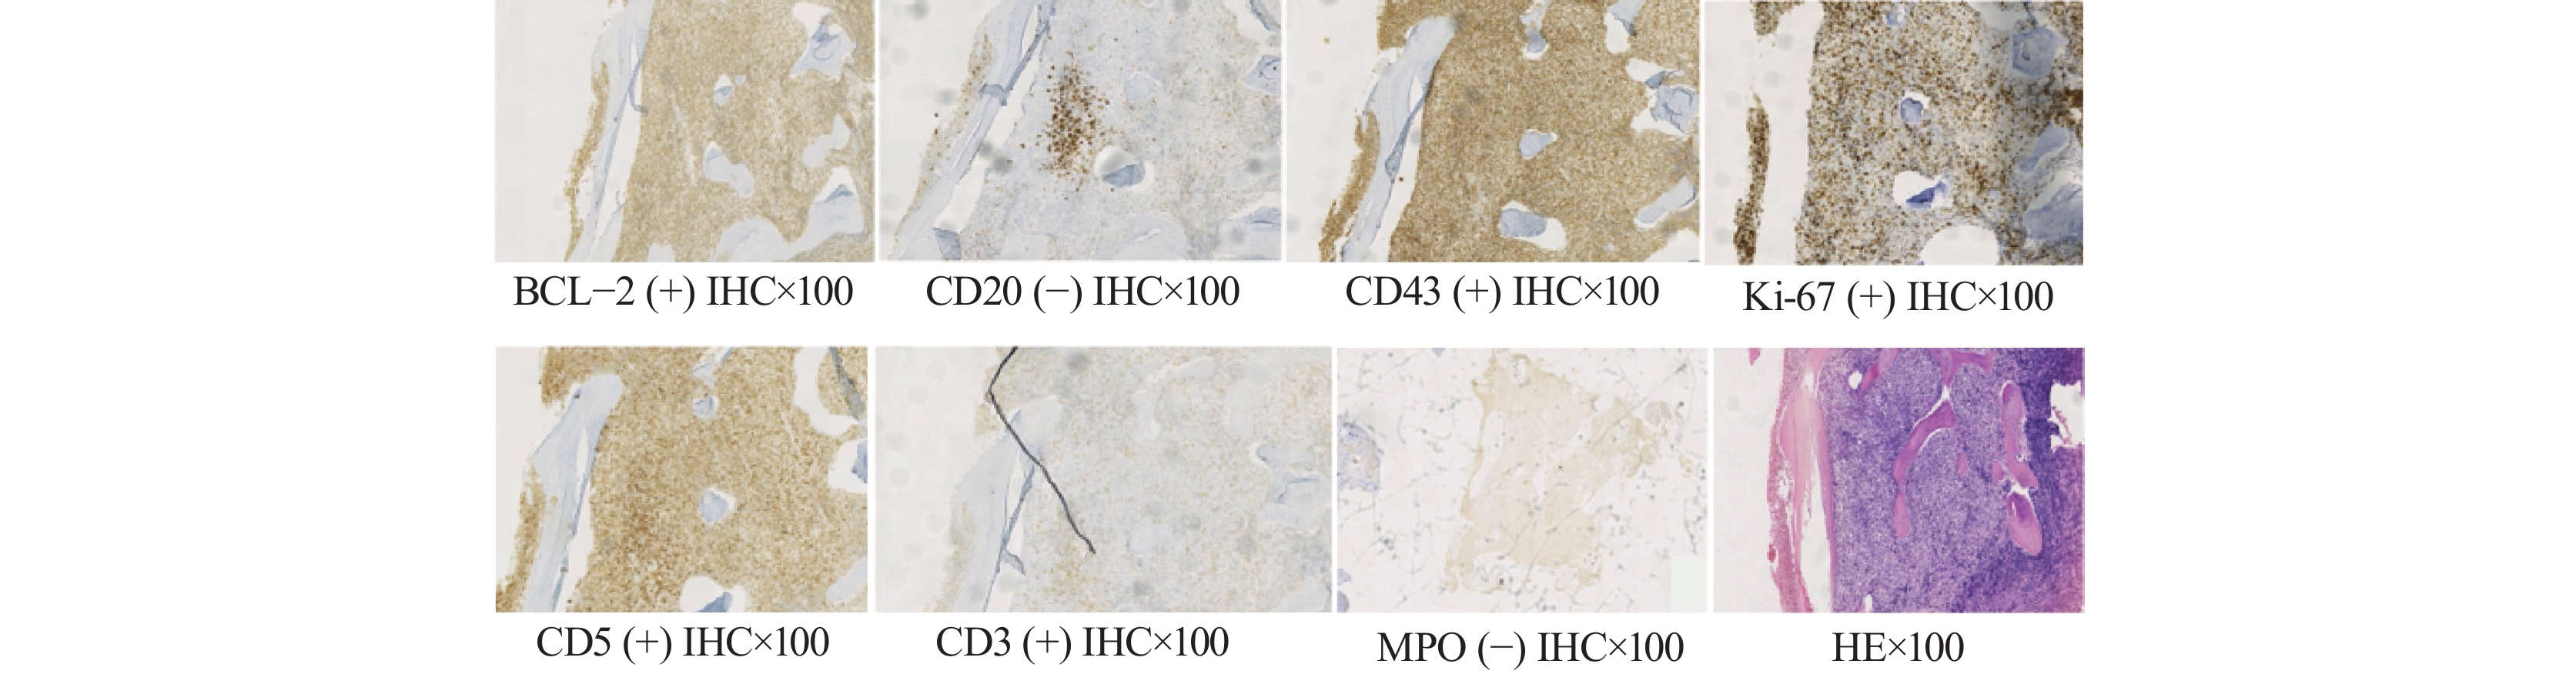

穿刺活检及病理结果显示髓腔内淋巴细胞增生性病变,细胞形态较一致,轻度异型,倾向非霍奇金T细胞淋巴瘤,免疫组织化学结果示:CD3(部分+),CD20(−),CD21(−),CD10(−),MUM-1(散在少量+)。CD23(−),CD5(+),CD43(+),CD38(少量+),cyclin D1(−),Ki-67(40%+),BCL-2(+),BCL-6(−),MPO(−),见图1。随后我们将病理组织样本送至山东大学齐鲁医院,明确诊断为外周T细胞淋巴瘤,免疫组织化学结果显示:CD79a(−),CD2(+),CD4(部分+),CD7(+),CD30(−),MPO(−),CD68(−),CD1a(−),EMA(−),TIA-1(−),CD8(少许+),CD56(−),CD123(−)。